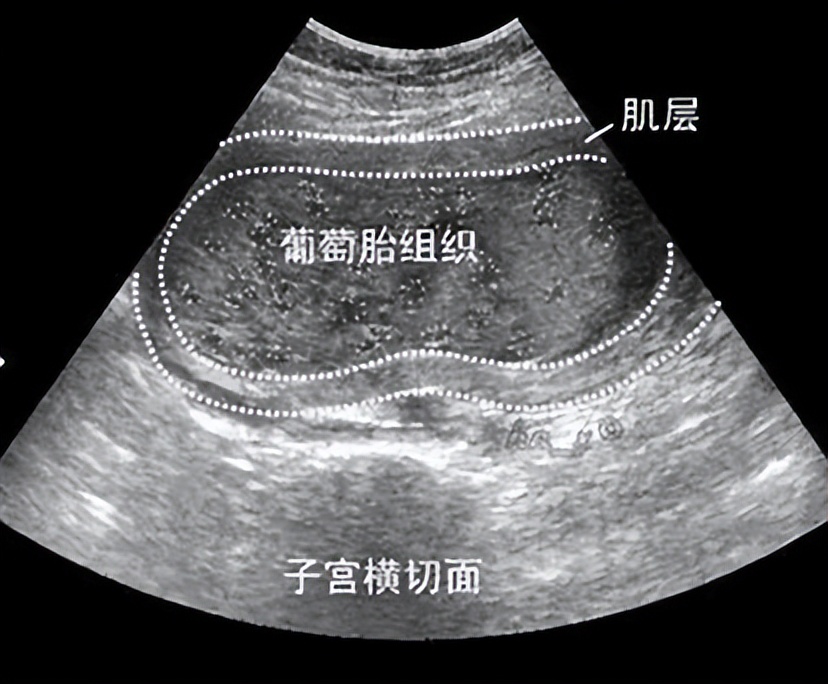

原来李女士怀孕后胚胎并不是正常胎儿,而且成串的葡萄样组织,医学上称为“葡萄胎”,是一种肿瘤。而发生葡萄胎时会出现妊娠孕吐严重的临床表现。因为增生的滋补细胞产生很多的人绒毛促性腺激素,所以孕吐通常比正常的妊娠重。

说到葡萄胎,很多人一听就觉得是怪胎,很可怕,但其实这只是一种异常妊娠,是一种疾病,并没有那么可怕。若发现葡萄胎,应立即终止妊娠,进行病理检查,在医生的帮助下及时治疗,治疗得当的话并不会影响正常的生育。